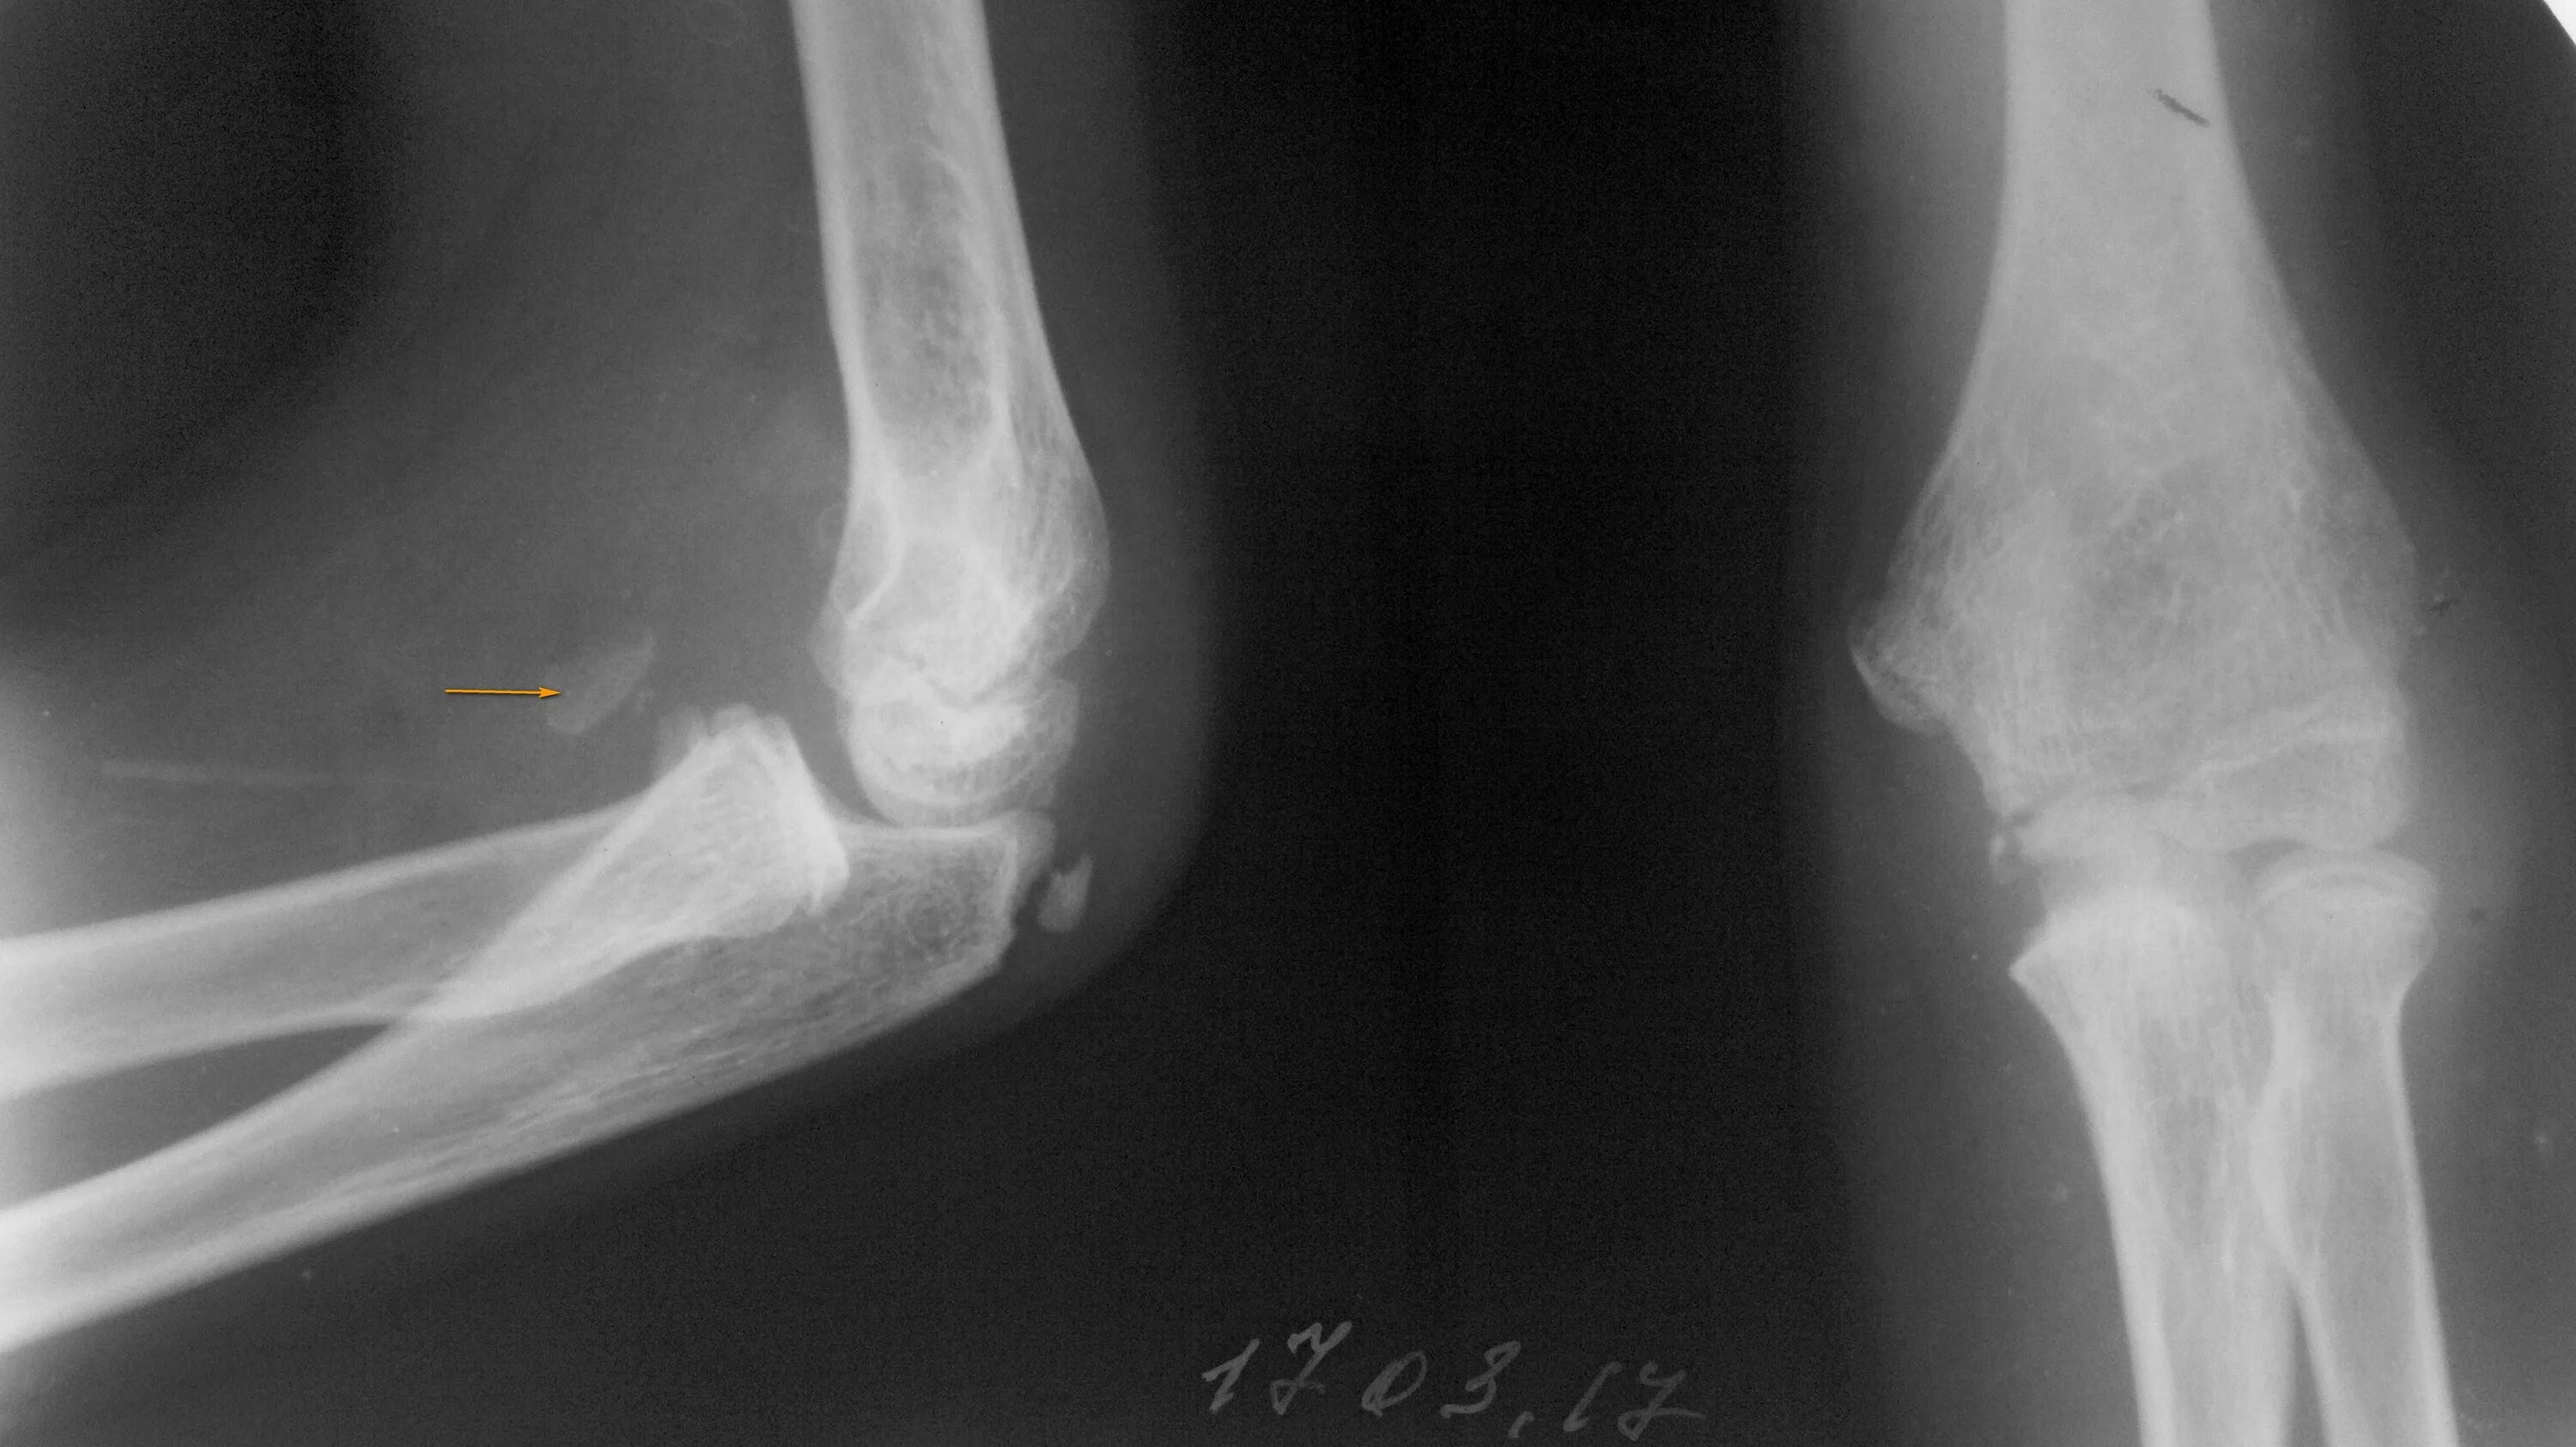

Перелом смещение локтя